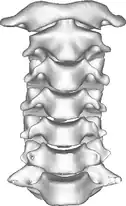

Once there is an onset of the symptoms in the patient, the patients are screened through cervical-spinal imaging techniques: X-ray, CT, MRI. The scanning technique points out any cervical vertebrae defects and misalignments. (Image 1. and 2.) When cervicocranial syndrome is caused as a result of a genetic disease, then family history and genetic testing aid in making an accurate diagnosis of cervicocranial syndrome.